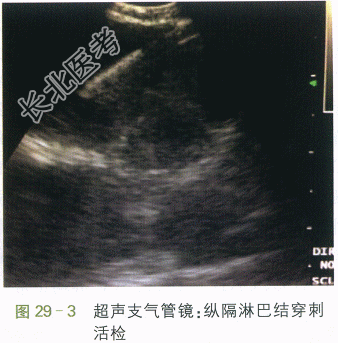

2.既往史 2014年患者有虹膜睫状体炎,治疗后好转;有过敏性鼻炎史。无吸烟嗜酒等不良嗜好,否认疫区驻留史。3.体格检查 全身皮肤无黄染,无肝掌、蜘蛛痣。全身浅表淋巴结无肿大,双肺叩诊清音,听诊呼吸音清。HR80次/min,律齐。腹部平软,肝脾肋下未及,肝肾区无叩击痛。4.实验室及影像学检查 血常规、出凝血功能、尿常规、肝肾功能、风湿全套、SACE等均正常,结核T淋巴细胞斑点(T-SPOT)试验:(-),24h尿钙9.98mmol/24h。胸部CT示:双侧肺门及纵隔多组肿大淋巴结,右肺中叶小结节。PET-CT示:右锁骨上、颈根部、纵隔、肺门及后腹膜糖代谢增高肿大淋巴结,右肺中叶小结节伴轻度糖代谢增高。常规心电图正常。患者入院后行支气管镜检查,发现双肺支气管黏膜弥漫性结节样突起(见图29-2),遂于左固有上叶支气管黏膜活检;并在超声引导下对隆突下淋巴结行穿刺活检术(EBUS-TBNA)(见图29-3)。术后病理:(左肺固有上叶及隆突下淋巴结)肉芽肿性病变伴小灶坏死,抗酸染色(-),糖原染色液(PAS)(-),六铵银染色(-),网染(坏死区网状纤维消失)。